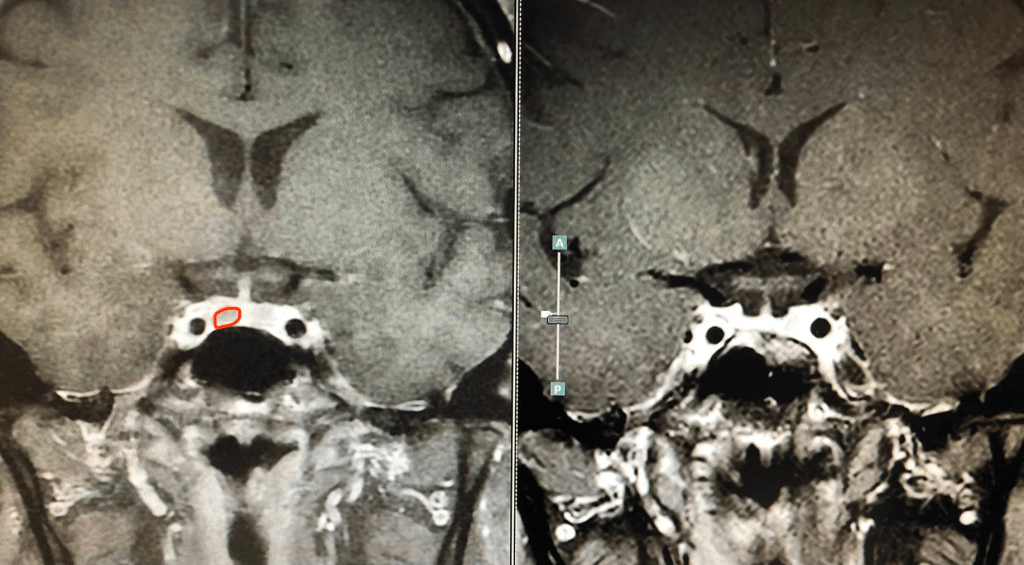

ผู้ป่วยรายนี้ได้รับการทำผ่าตัดโดยการส่องกล้องผ่านทางโพรงจมูกและนำเนื้องอกออกจนหมดโดยเก็บเนื้อต่อมใต้สมองส่วนอื่นไว้ได้ หลังผ่าตัดผู้ป่วยระดับฮอร์โมนต่ำตั้งแต่วันแรกๆ ระดับความดันกลับเป็นปกติสามารถหยุดยาความดันได้ทุกตัว น้ำหนักตัวลดจาก 67 เป็น 41 กิโลกรัม ไม่มีการขาดฮอร์โมนอื่นเพิ่มเติม 4ปีหลังผ่าตัดผู้ป่วยมีชีวิตเป็นปกติและไม่ต้องอาศัยการรักษาอื่นร่วมด้วยเลย

ผู้ป่วยรายนี้ผลฮอร์โมนกลับเป็นปกติหลังผ่าตัด